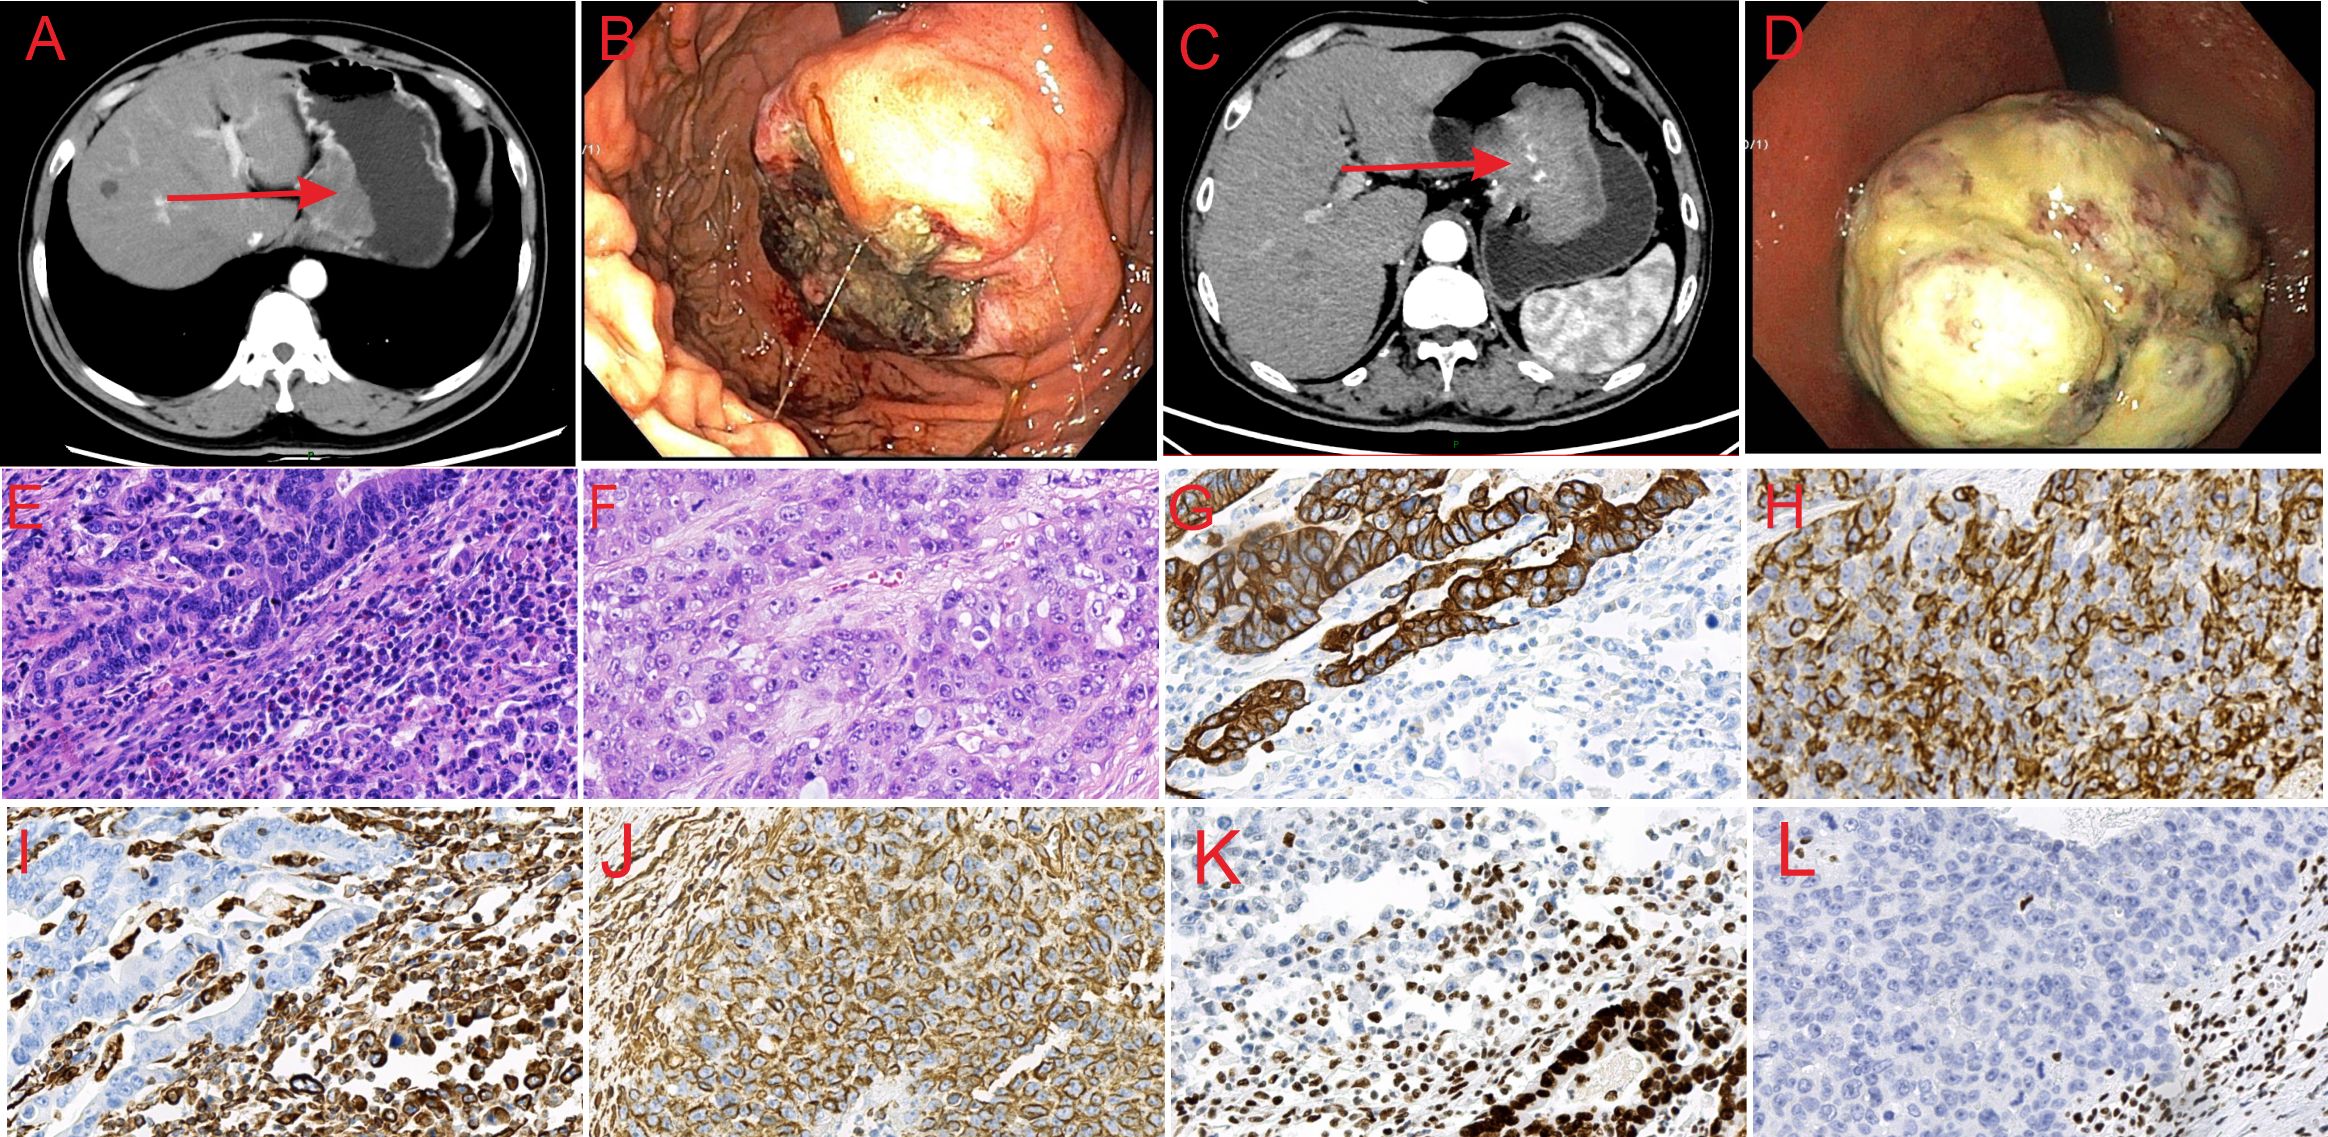

Figure 1. Abdominal CT, endoscopic and histological features of the lesions. (A) CT image of SMARCA4-deficient carcinosarcoma showing thickening of the lower esophageal segment and gastric cardia wall. (B) CT image of SMARCA4-deficient sarcomatoid carcinoma showing thickening of the gastric lesser curvature and side-cardia wall, with an irregular mass shadow. (C) Endoscopic image of SMARCA4-deficient carcinosarcoma showing a large, protruding lesion on the gastric fundus mucosa, with a ruptured surface. (D) Endoscopic image of SMARCA4-deficient sarcomatoid carcinoma showing a large, protruding lesion near the gastric fundus on the lesser curvature. (E) Microscopic image of SMARCA4-deficient carcinosarcoma (HE, ×40). (F) Microscopic image of SMARCA4-deficient sarcomatoid carcinoma (HE, ×40). (G) CK staining shows positive expression in the adenocarcinoma area and negative expression in the sarcoma area of SMARCA4-deficient carcinosarcoma (×40). (H) CK staining showing positive expression in SMARCA4-deficient sarcomatoid carcinoma (×40). (I) Vimentin staining showed negative expression in the adenocarcinoma area and positive expression in the sarcoma area of SMARCA4-deficient carcinosarcoma (×40). (J) Vimentin staining showing positive expression in SMARCA4-deficient sarcomatoid carcinoma (×40). (K) SMARCA4 staining showing positive expression in the adenocarcinoma area and negative expression in the sarcoma area of SMARCA4-deficient carcinosarcoma (×40). (L) SMARCA4 staining showing negative expression in SMARCA4-deficient sarcomatoid carcinoma (×40).

The patient underwent radical total gastrectomy with esophagojejunostomy, but declined postoperative adjuvant treatment. Lymph nodes no. 1, 2, 3, 5, 6, 7, 8, 9 and 11 were removed during the operation. The tumor measured approximately 7 cm × 6 cm. Histopathological analysis revealed a mixed tumor composed of moderately differentiated adenocarcinoma and sarcoma. In the adenocarcinoma region, cancer cells formed glandular tubular structures with fibrinoid necrosis. The boundary between the adenocarcinoma and sarcomatous areas was unclear. Sarcomatous cells were loosely arranged, spindle-shaped, uniform in size, and displayed bizarre nuclei, numerous mitotic figures, rich cytoplasm, eccentric nuclei, large nuclei, obvious nucleoli, and many inflammatory cell infiltrations (Figure 1E). The tumor invaded the entire thickness of the gastric wall and the nerve. Cancer emboli were observed in the vessels. There were three lymph node metastases: one was an adenocarcinoma, and two were sarcoma components. Immunohistochemistry revealed that CK (Figure 1G), EMA, and SMARCA4 (Figure 1K) were positively expressed in the adenocarcinoma area, whereas Vimentin (Figure 1I) was negative; CK (Figure 1G), EMA, SMARCA4 (Figure 1K), ERG, Desmin, CD34, HMB-45, S100, CK7, CK5/6, and p40 were negatively expressed in the sarcoma area, while Ki-67(+50–60%), Vimentin (Figure 1I), and INI-1 were positively expressed. The final diagnosis was carcinosarcoma with a SMARCA4 deficiency in the sarcoma area; pT4N2M0.

The tumor measured approximately 10 cm × 8 cm. Microscopically, the tumor cells were arranged disorderly, without the structural hierarchy of normal tissues. They contained cancerous and sarcomatoid components. The cancerous component contained moderately differentiated epithelial-like nest cells, while the sarcomatoid component featured diffuse spindle growth cells invading the entire thickness of the gastric wall (Figure 1F). Cancer emboli were detected in the vessels. CK (Figure 1H), Vimentin (Figure 1J) and Ki-67 (>75%) were positive in the tumor cells, whereas SMARCA4 (Figure 1L), CD20, LCA, CD3, HMB-45, Melan-A, Epstein-Barr virus (EBV) were negative. Mismatch repair proteins were intact. The final diagnosis was SMARCA4-deficient sarcomatoid carcinoma; pT4N1M0.